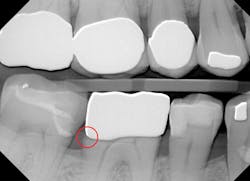

The majority of patients have two primary concerns with any indirect restorative procedure: (1) is it worth the sizable financial investment, and (2) how comfortable or painful will it be? With unadjusted proximal contacts, this procedure has failed on both counts. Based on the 2013 Survey of Dental Fees from the American Dental Association,1 the patient has spent roughly between $800 and $1,400 on a restoration that is short-lived, uncomfortable, and necessitates further treatment and discomfort (figure 1).

Figure 1: Incomplete marginal seating due to overly tight proximal contacts.